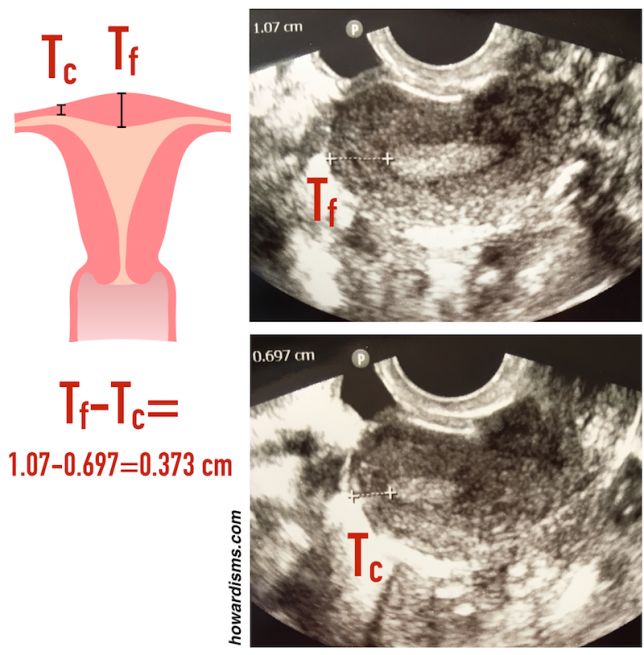

2. Beware of the false positives.

One of the most common reasons for an HSG today is to check for tubal patency. Office-based saline-infusion sonography (SIS), especially when combined with a 3D reconstruction, is very effective for providing views of the uterus and cavity and this study (so-called virtual hysteroscopy) has essentially replaced HSG for exploring uterine malformations, Asherman Syndrome, etc.

Thus, HSG today is commonly used to check for tubal occlusion following an Essure sterilization or to check for tubal patency as part of a workup of infertility. How accurate the test is will vary based upon the pretest probability of tubal occlusion for a given patient. Swart et al. determined that the point sensitivity for HSG (compared to chromopertubation) was 0.65 with a specificity of 0.83 for tubal blockage. Consider three patient situations:

Using the above sensitivity and specificity, the following positive and negative predictive values would be calculated:

These numbers are very important and highlight one of the leading problems in clinical medicine: Incorrect diagnoses often occur because the pretest probability isn’t considered when determining predictive values of the test. If the patient has had an Essure and both coils are visualized in the appropriate location, then despite the rather high rate of tubal spasm that can occur with an HSG (about 1/3), the positive predictive value is still on the order of 99.7%. On the other hand, if the patient is being evaluated for secondary infertility and the test shows a blocked tube, the positive predictive value is only 61% (as compared to the gold standard of chromopertubation).

The real trouble happens when an HSG is done on an average, random woman who has nothing that would elevate her pretest probability for tubal occlusion. In this case, the result of blocked tube on HSG would carry only a 10.6% chance of actual tubal occlusion. Most of the apparent blocked tubes are the result of tubal or cornual spasm rather than true pathology. This statistic is particularly important as FemVue becomes more common in office practice.

FemVue (an agitated saline-infusion device) is used with ultrasound to test tubal patency in the office. It performs roughly as well as HSG when compared to chromopertubation in terms of sensitivity and specificity. The problem is that its use has been expanded in many cases to an inappropriate patient population. For example, some clinics perform it routinely on all fertility patients even if they have another underlying cause of infertility already established (like anovulation). In this case, the pretest probability of tubal occlusion (assume the woman has no history of chlamydia, etc.) is similar to that of a random woman. When tubal occlusion is noted on FemVue in a patient like this, the positive predictive value is close to 10%. So, in some populations, about 90% of positive results are false positives. This is a dangerous consequence of indication drift and a poor understanding of the role that pretest probability plays in determining the predictive value of a test.